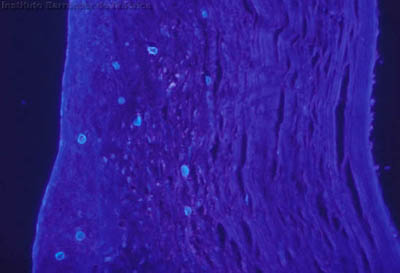

Microscopía Confocal

Preparaciones de extendido en capa sobre laminilla con agua destilada sin colorear, en campo claro y bajo contraste de fases: permite buena visualización de las formas Quísticas de Acanthamoeba

Magnificación 160x

Tinción CW

Blanco de Calcofluor + Azul de Evans

Tinción Giemsa

Tinción PAS

(Acido Periodico de Schiff)

Tejido corneal Procesado

H&E

PAS

CW